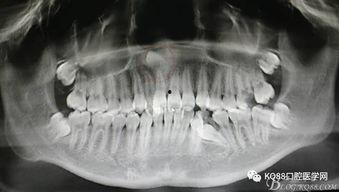

视频中,我们可以看到医生如何通过X光片确定多生牙的位置,然后进行局部麻醉。麻醉过后,医生使用专业的工具将多生牙从牙床中取出。整个过程大约需要30分钟左右。

1. 术前准备:医生首先通过X光片确定多生牙的位置,然后为患者进行局部麻醉。